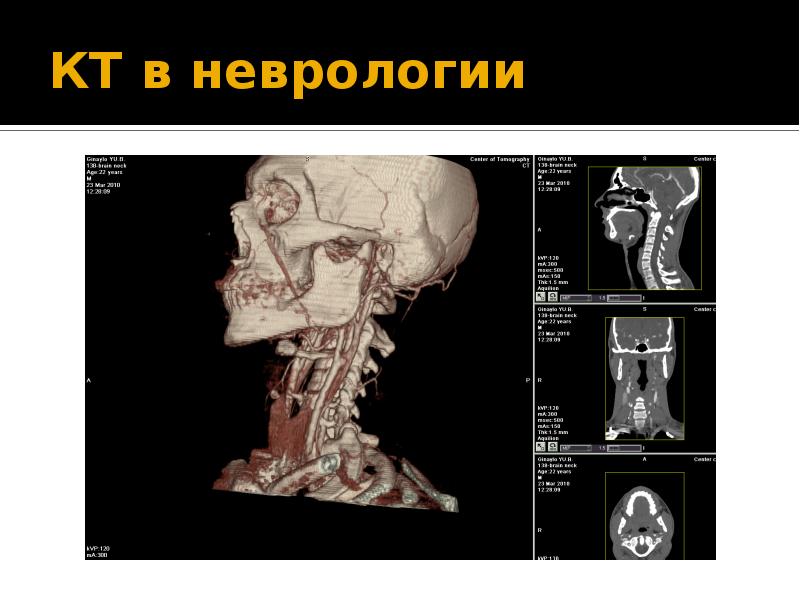

Компьютерная томография в неврологии презентация - 86 фото